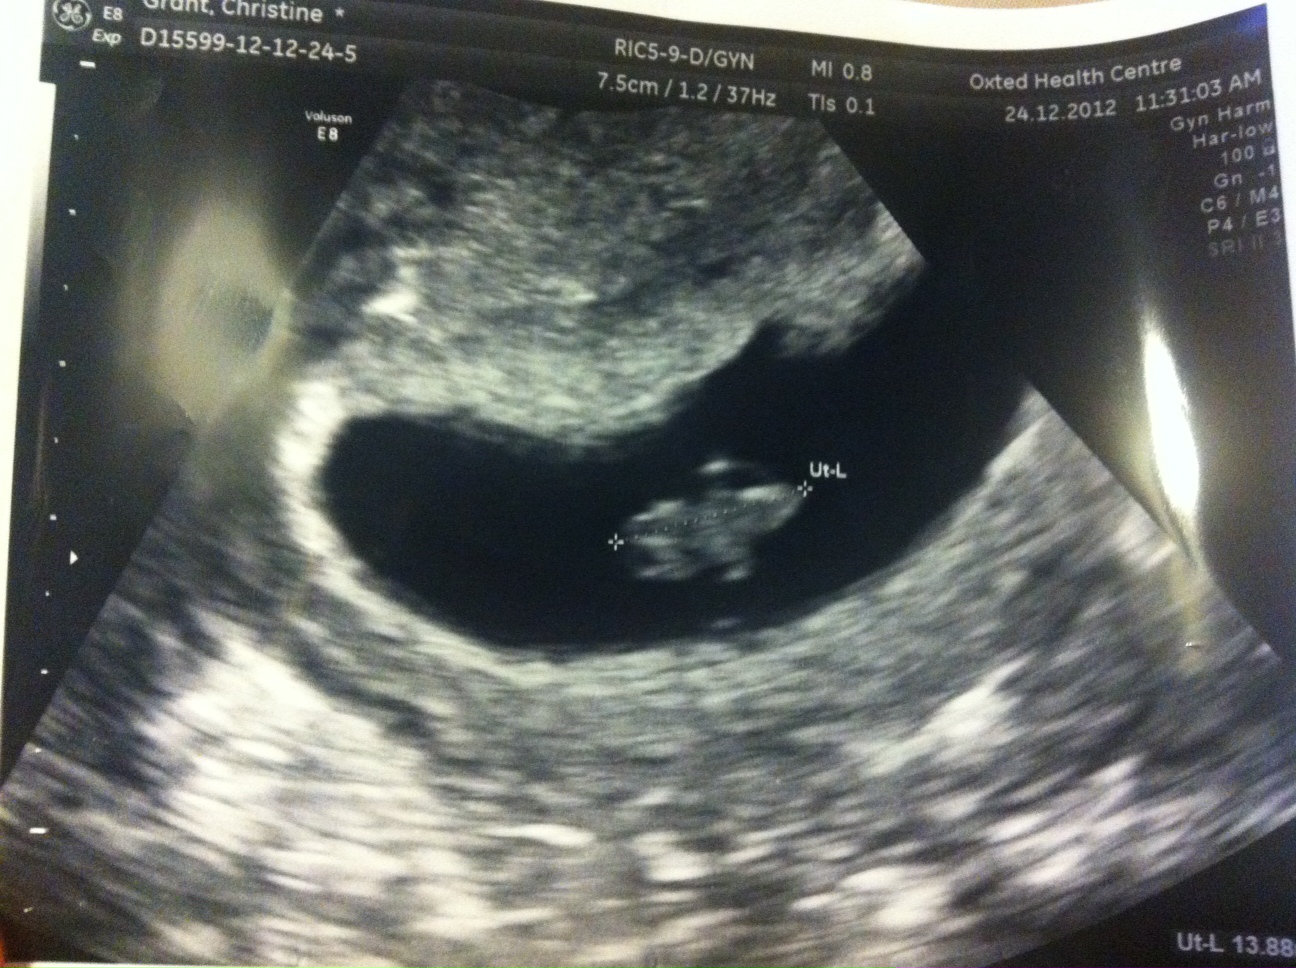

These are the pictures I got:

Attachment 7590

I then had a second (private) scan 6 days later and there were still 2 sacs yet this time it appeared there was a healthy baby in the big sac with yolk sac and heart beat and a CRL measurement of 13.8mm making it 7+5. The smaller sac still had an embryo and a tiny fetal pole but no heartbeat measured 3.6mm